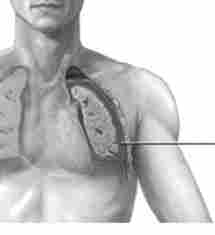

Мал. 25.5. гемоторакс

Гемоторакс. Гемоторакс - скупчення крові в плевральній порожнині (рис. 25.5). Причина травматичного гемоторакса - закрита або відкрита травма грудної клітини з пошкодженням міжреберних і внутрішньої грудної артерій, органів грудної порожнини (легень, серця, діафрагми).